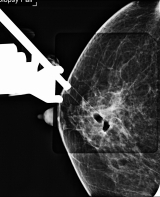

◆침대형 입체정위 진공절제술 통해 보다 쉽게 제거

과거에는 석회화는 외과적 수술로 조직검사를 해야하다보니 유방에 큰 흉터가 남게 되는 경우가 많았지만, 최근에는 입체정위 진공절제술을 통해 흉터가 거의 없이 석회화를 절제할 수 있게 됐다.

이 병원장은 "입체정위 진공절제술은 컴퓨터 계측장치를 이용해 유방내의 석회화의 위치를 확정하고, 그 위치에 맘모톰이라고 통칭되는 진공보조장치를 삽입해 석회화를 절제하는 방식"이라면서 "최근에 개발된 3차원 입체정위법, 즉 디지털 유방단층합성법은 기존의 2차원 입체정위법에 비해 더 정확하게 석회화 위치를 정할 수 있고, 시술시간이 짧으면서 방사선 피폭량도 적다는 장점이 있다"고 덧붙였다.

예전의 입체정위 조직검사장치는 유방촬영장치에 부착해 사용했다. 이렇게 되면 환자가 선 자세에서 시술을 받아야 하다 보니 아무리 정확하게 위치를 설정했다 하더라도 환자의 움직임에 따라 변동이 생길 수밖에 없다. 여기에다 시술 과정을 환자가 직접 보게 되면서 환자가 미주신경반사에 의해 실신하는 경우도 있었다.

하지만 최근에는 침대형 시스템이 도입되면서 이 같은 단점을 상당히 보완하게 됐다. 환자는 10~20분 동안 엎드려 있는 것만으로 편안하게 시술을 받을 수 있게 된 것이다. 이 병원장은 "기존 부착형은 접근 방향이 제한적이라는 한계도 있었지만, 침대형은 360도 어느 방향에서 접근이 가능하다는 장점도 있다"고 했다. 다만 유방의 두께가 2cm 이하로 유방이 작은 경우, 석회화 병변이 아주 작거나 흉벽 혹은 유두 근처 등 유방의 가장자리에 위치한 경우에는 이 시술이 불가능하다.